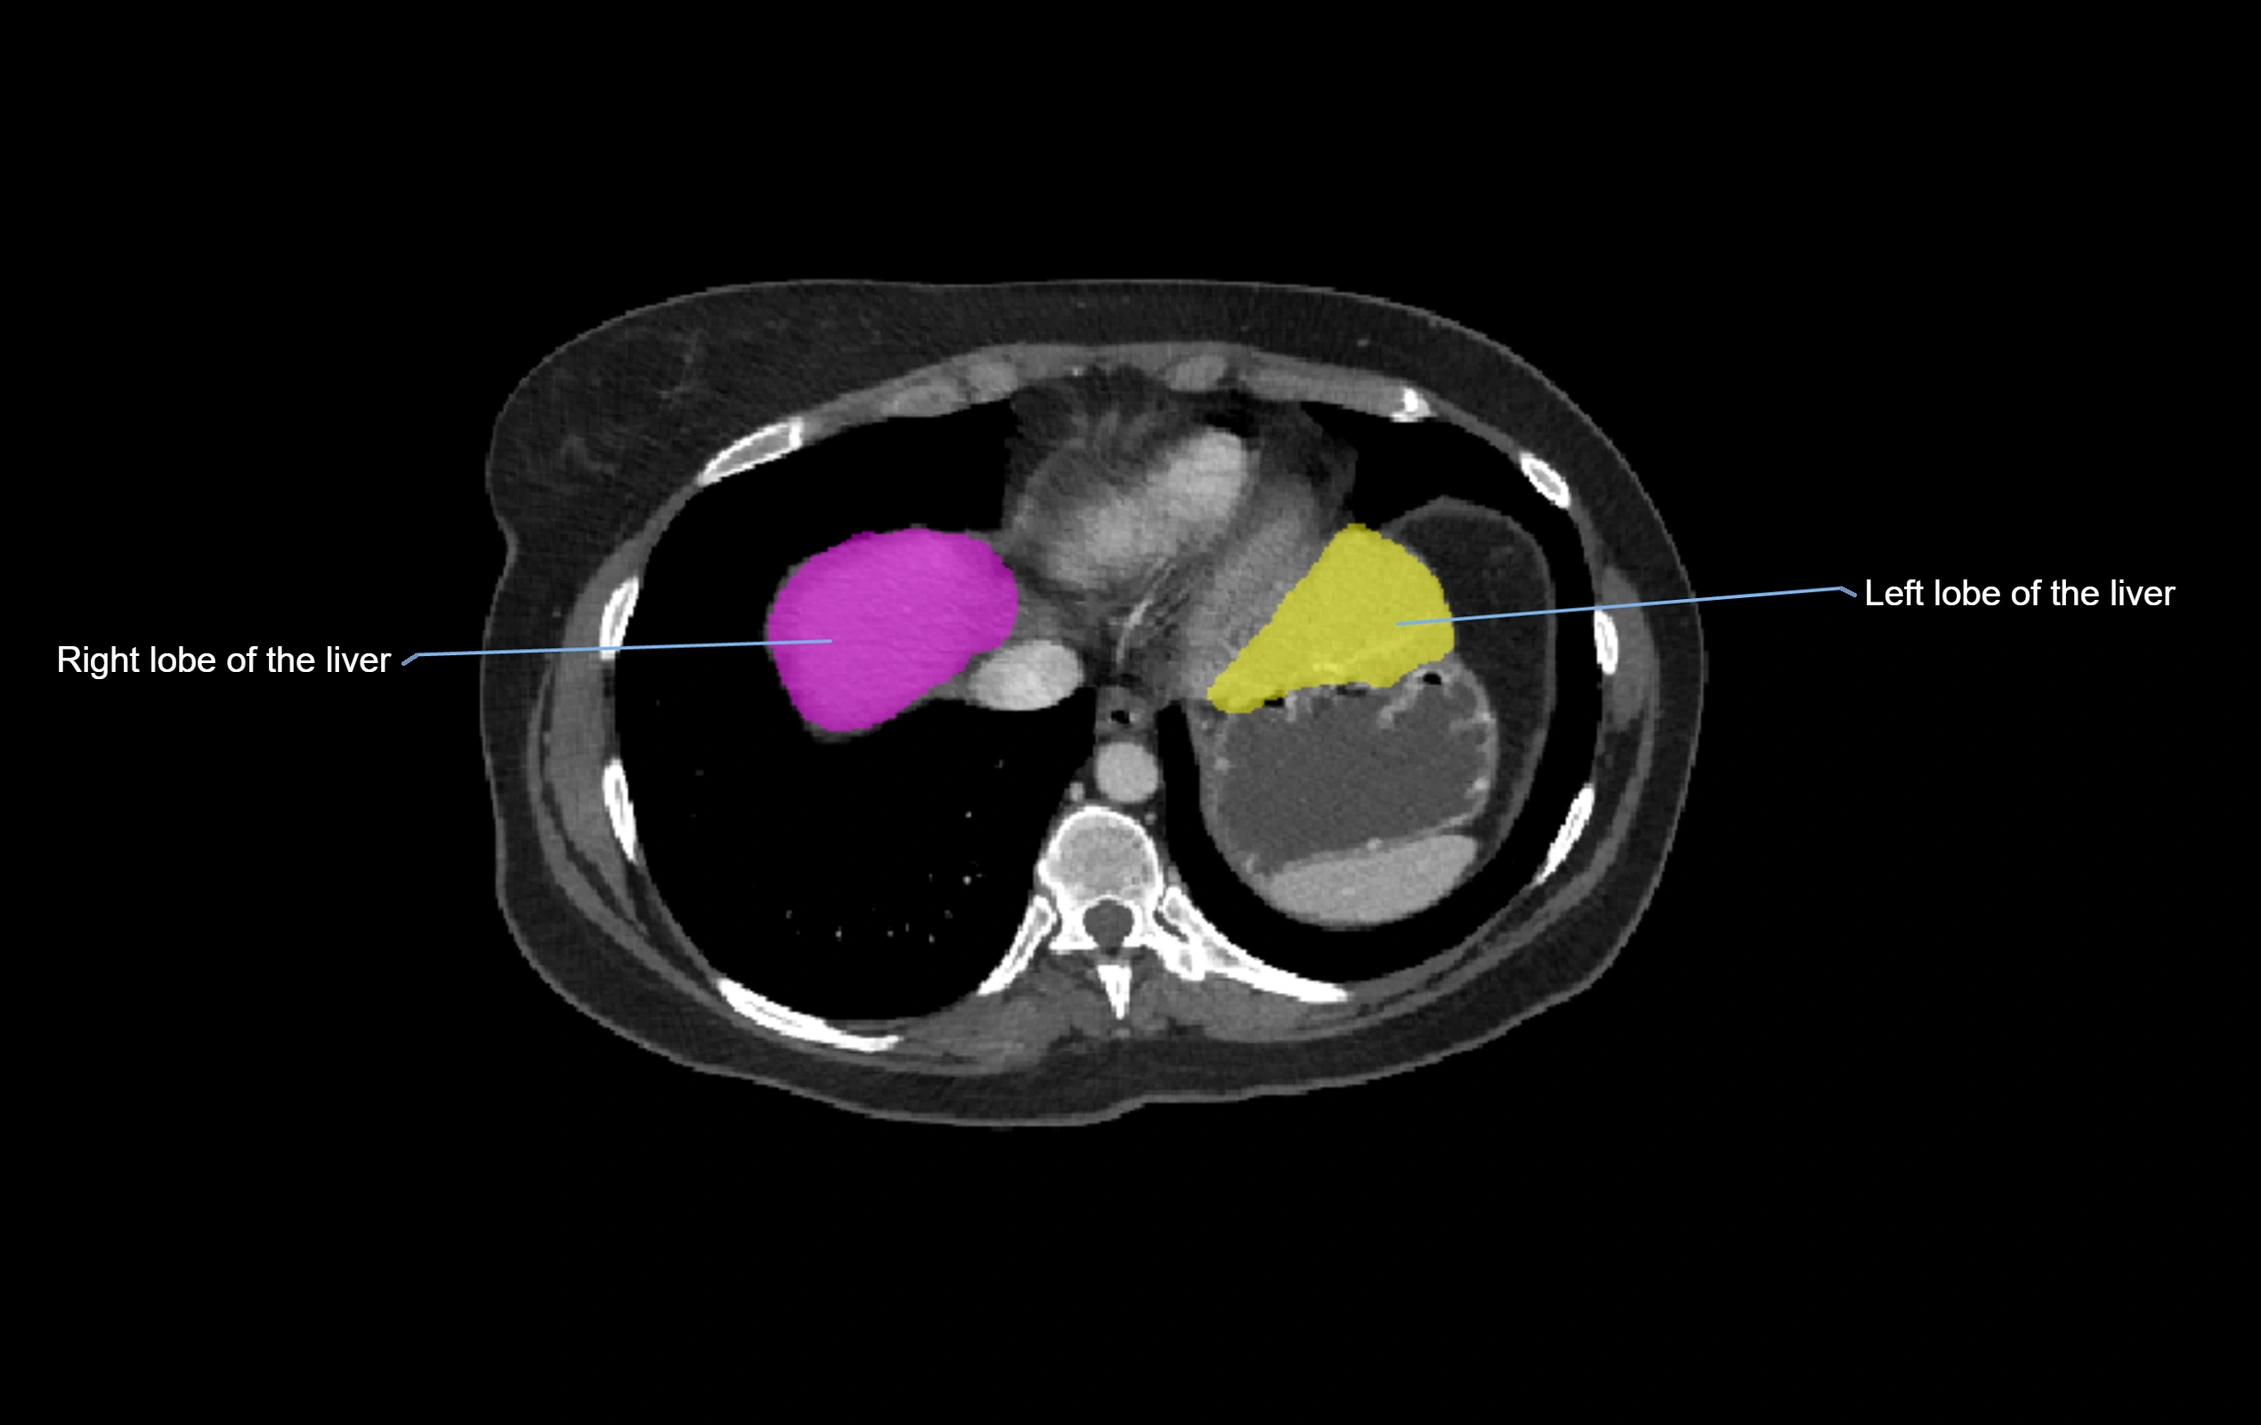

MRI image

image